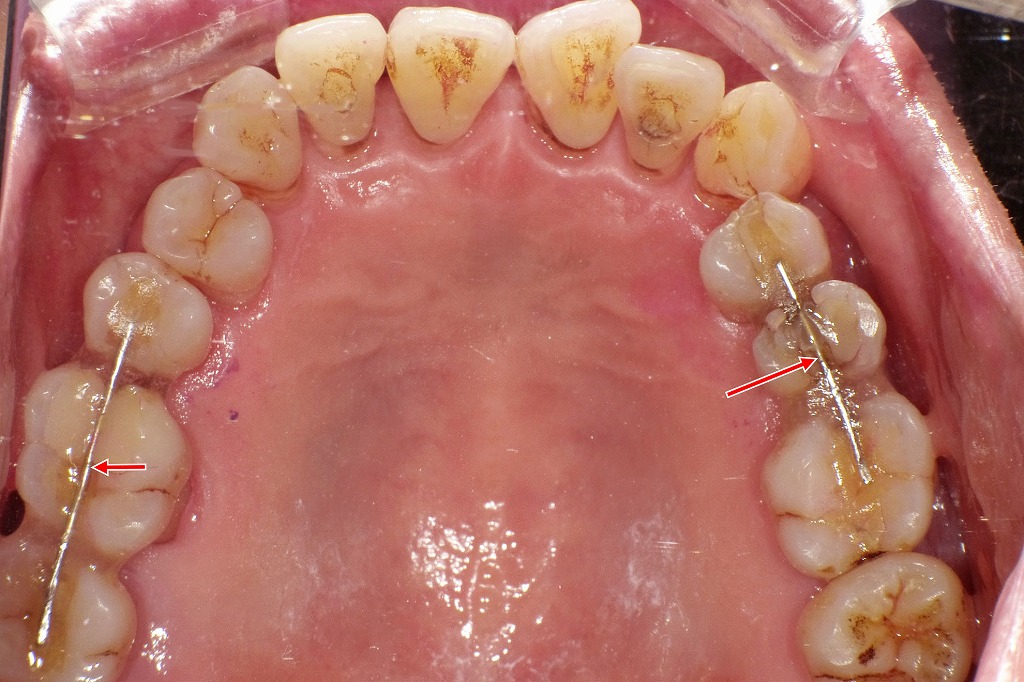

👀上下咬合面観

重度歯周病治療後の上顎咬合面観です。臼歯部では歯槽骨吸収が高度で、咬合時の不安定性(動揺)が認められました。

咬合力の分散と歯の安定を目的として、咬合面にワイヤーを配置し、スーパーボンドを用いた暫間固定を行っています(矢印部)。この処置により、日常の咀嚼時の負担を軽減しながら、歯周組織の長期的な維持管理を図っています。

重度歯周病治療後の下顎咬合面観です。下顎では歯槽骨吸収は上顎に比べて比較的軽度で、全体の支持状態は保たれています。

動揺が認められた前歯部に限って、スーパーボンドを用いた暫間固定を行い(矢印部)、咬合時の安定性を確保しています。臼歯部は固定を必要としない状態で、現在は良好なプラークコントロールのもと、歯周組織は安定しています。